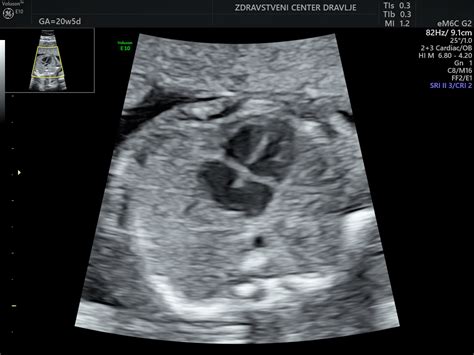

Pomembno je vedeti, da so govorice o tem, da oblika trebuha (na primer špičast ali bolj zaobljen) nakazuje na spol otroka, zgolj babje čenče in nimajo znanstvene podlage. Samo na podlagi oblike trebuha ne moremo podati smernic o otrokovem spolu. Slednje lahko izveste le na ultrazvočnem pregledu, po 11. tednu nosečnosti.

V prvem trimestru razvoj ploda poteka od oplojene jajčne celice do fetusa, ki na koncu prvega trimestra že ima vse vitalne organe. Telo nosečnice se začne prilagajati na novo stanje. Pregledi v prvem trimestru: laboratorijske analize krvne slike, krvnega sladkorja na tešče, krvne skupine in Rh faktorja, test na toksoplazmo gondi in sifilis, ultrazvočna potrditev nosečnosti do 11. tedna in pregled nuhalne svetline (ki ga stroka priporoča) se opravi med 11. in 14. tednom nosečnosti.